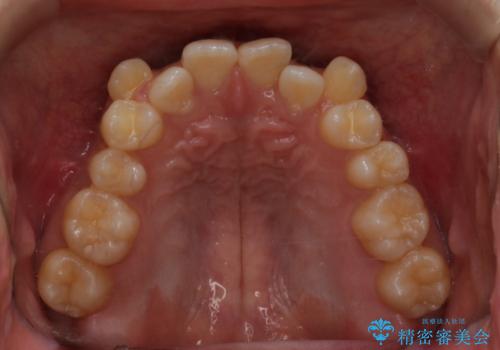

インビザライン単独でここまでできる!!抜歯矯正

- 治療計画

1日20時間以上、正しくインビザラインを使用して頂いたおかげで、ワイヤーに切り替えることなく矯正治療を終了することが出来ました。周囲からも歯並びがすごく綺麗になったと言われたのことで大変ご満足いただけました。